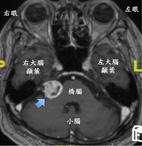

張先生,68歲有高血壓病史但規則服用藥物治療,血壓控制穩定,近三個月來感覺到右耳聽力減退、暈眩以及走路不穩,症狀有逐漸加重的現象,於是他到本院耳鼻喉科門診求助。經過聽力檢查確認右側聽力變差,腦幹聽覺誘發電位檢查也發現右側聽神經的神經傳導異常,懷疑可能是聽神經瘤造成,之後再經腦部磁振造影檢查發現於右側小腦橋腦角處有個約2.4公分大的聽神經瘤(如:圖一),張先生被轉介至放射腫瘤科門診進一步評估及治療。

圖1. 磁振造影顯示橋腦與小腦右側有直徑約2.4公分的聽神經瘤(藍色箭號)